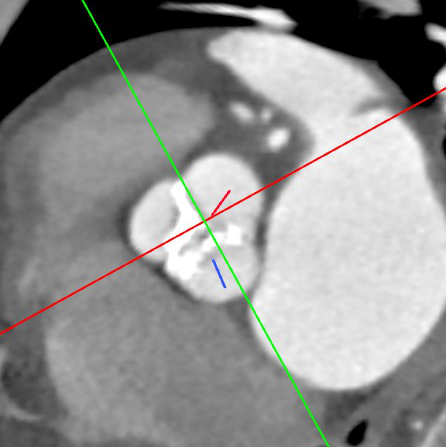

CT评估:

瓣环周长74.6mm,左室流出道周长79.4mm,左冠高度9mm(瓣叶长14mm),右冠高度10mm(瓣叶长11mm),窦宽31/29/30mm,STJ距瓣环高度14.5mm,最大直径约27.6mm。

横切面

患者三叶瓣,瓣叶增厚,右窦、无冠窦钙化严重,形态分布可能导致术后仍有轻度瓣周漏;右冠瓣瓣叶长,右冠开口处可见瓣叶且靠近瓣叶交界,且右窦钙化分布会将瓣膜往左侧推,结合ST-J高度和大小,冠脉风险较高,需22mm球囊预扩评估。

经团队评估,结合根部形态及病情等因素,决定选用VitaFlow Liberty™电动可回收瓣膜输送系统,22mm球囊预扩,预装TAV27瓣膜,体循干备。计划植入深度1-2mm。